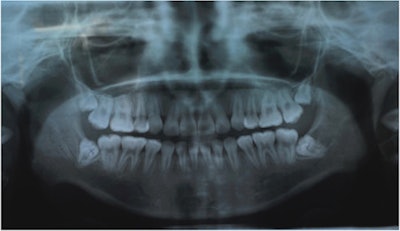

A 17-year-old girl with no significant past medical history went to an oral and maxillofacial surgery clinic to have her impacted wisdom teeth extracted. Surgically removing her mandibular third molars was considered a routine procedure.

A distal "hockey stick" incision was used to raise the mucoperiosteal flap to get to the crowns, which were lingually inclined. The nerves were intact, and the teeth were removed with no excessive bleeding, according to the report.

Three days later, the girl returned complaining of right facial swelling and bruising, pulsating pain, malaise, and fever. An intraoral exam revealed very inflamed soft tissue around the residual socket of extracted tooth #32 that was bleeding spontaneously and was tender to touch, they wrote.